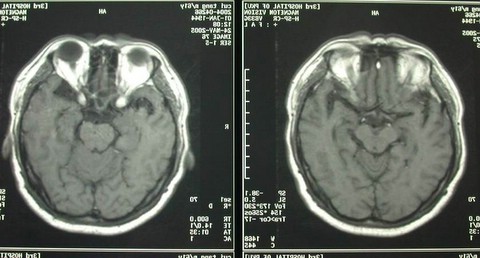

男性,60岁,主因双眼视力下降2个月入院,查MRI示:鞍区巨大占位。

诊断考虑垂体腺瘤。行经鼻蝶手术,全切肿瘤,术后复查如下: